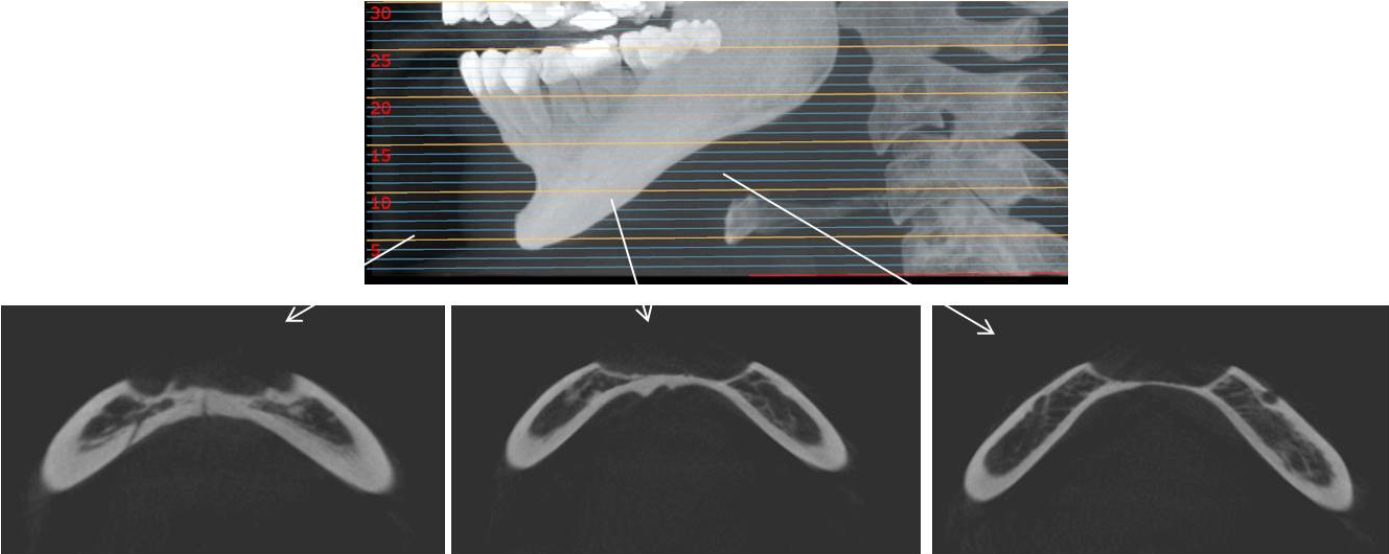

32세 여성 환자의 파노라마방사선영상에서 하악 전치부 낭이 관찰되어, 정확한 진단을 위하여 본원에 의뢰되었다. 특별한 임상증상은 없었다. 파노라마방사선영상에서 하악 우측 제1소구치에서 좌측 제1소구치 치근하방에 경계가 명확하고 피질골성 변연을 가진 타원형의 방사선투과상이 관찰되었다(Fig. 1). 방사선투과상은 해당치아들과는 무관하여 치근단낭이 배제되었고, 단순골낭의 가능성을 염두에 두고 콘빔CT 검사를 시행하였다. 콘빔CT에서 중심성 골내 병소가 아닌 악골의 순측에서 설측으로 함몰된 변연성 병소가 관찰되었다(Fig. 2). 병소의 경계는 매우 평활하였고, 단면상에서는 넓은 접시모양처럼(Fig. 3), 악골 절단면상에서는 반달모양처럼 함몰되어 있었다(Fig. 4). 설측 피질골은 비박되어 있었으나 천공은 관찰되지 않았다. 함몰된 부위는 공기가 아닌 연조직의 방사선투과상으로 채워졌으나, 콘빔CT에서는 대조도가 낮아서 연조직간의 감별이 가능하지 않았다(Fig. 5). 관찰된 턱 끝 부위의 골 함몰이 해부학적 변이인지 아닌지를 감별하기 위하여 환자의 과거 병력을 알아보았다. 환자는 2년 전에 턱 끝 부위에 미용 필러 시술을 받았다고 하였다. 방사선영상소견과 문진결과를 토대로, 미용 필러와 관련된 골흡수를 의심하였다. 이후 외과적으로 미용 필러 제거와 함몰된 부위에 골이식이 시행되었다. 수술 중에 육안으로 남아있는 미용 필러와 작은 석회화 물질들이 확인되었다. 수술 후 생검에서 다핵거대세포와 결절석회화가 관찰되었고, 피부석회화(calcinosis cutis)가 의심된다는 결과를 받았다. 이상의 술 전 검사 및 술 후 소견을 종합하여, 파노라마방사선영상에서 관찰된 방사선투과상은 치성낭이나 해부학적 변이가 아니고 미용 필러에 의한 하악골 순측 골흡수로 최종 진단되었다.

Cone-beam computed tomographic cross-sectional view of the mandible clearly demonstrates a peripheral bone depression extending from the labial to the lingual cortical plate.